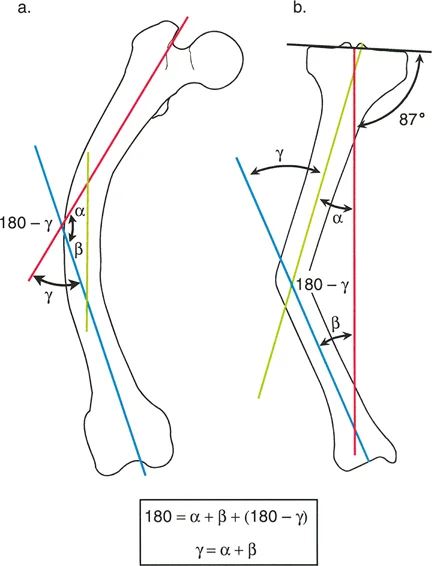

محور تصحيح الزاوية (ACA)

بينما يعتبر CORA حقيقة تشريحية ثابتة، فإن ACA يقع جزئيًا تحت سيطرة الجراح. يمثل ACA النقطة المحورية التي يدور حولها الجزء البعيد من العظم لتحقيق التصحيح.

* الموضع الأمثل: يجب أن يكون ACA موجهًا بشكل عمودي على مستوى التشوه ويمر مباشرة عبر CORA.

مستوى قطع العظم (Osteotomy Level)

مستوى قطع العظم (الشق الجراحي) يقع بالكامل تحت سيطرة الجراح. تحدد العلاقة الهندسية بين مستوى قطع العظم، وACA، وCORA النوع الدقيق للتصحيح الناتج، وتحدد ما إذا كان سيحدث تشوه ثانوي غير مقصود (مثل الانزياح غير المرغوب فيه).

إن فهم العلاقة المكانية بين القطع، والمفصلة، وقمة التشوه هو سر التصحيح الخالي من العيوب. تحدد قواعد بالي لقطع العظم النتائج الميكانيكية لخطتك الجراحية:

القاعدة الذهبية الأولى: القطع والمفصلة عند مركز الانحراف

عندما يمر كل من قطع العظم وACA مباشرة عبر CORA، يتم تصحيح التشوه الزاوي بشكل مثالي. يتم استعادة المحور الميكانيكي، ولا يوجد انحراف في المحور الميكانيكي (MAD)، وتبقى أجزاء العظم القريبة والبعيدة متوازية تمامًا. هذا هو السيناريو المثالي، والذي غالبًا ما يتحقق بقطع عظم وتدي بسيط (فتح أو إغلاق) عند قمة التشوه.

القاعدة الذهبية الثانية: المفصلة عند مركز الانحراف والقطع بمستوى مختلف

في بعض الأحيان، قد يكون قطع العظم مباشرة عند CORA غير ممكن سريريًا بسبب سوء حالة الجلد، أو وجود أدوات جراحية سابقة، أو مشاكل في جودة العظم في منطقة الكردوس/الجذع. إذا بقي ACA عند CORA، ولكن تم إجراء قطع العظم عند مستوى مختلف (أقرب أو أبعد عن CORA)، فسيتم تصحيح التشوه الزاوي بالكامل. ومع ذلك، ستنزاح نهايات العظم عند موقع قطع العظم بالنسبة لبعضها البعض.

* النتيجة السريرية: يؤدي هذا إلى "نتوء" أو تعرج في المحور التشريحي، لكن المحور الميكانيكي العام وتوجيه المفصل يظلان متوائمين تمامًا.